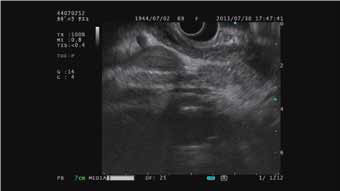

与凸阵扫描超声支气管镜配套使用

B-模式 H-FLOW模式 ELST模式